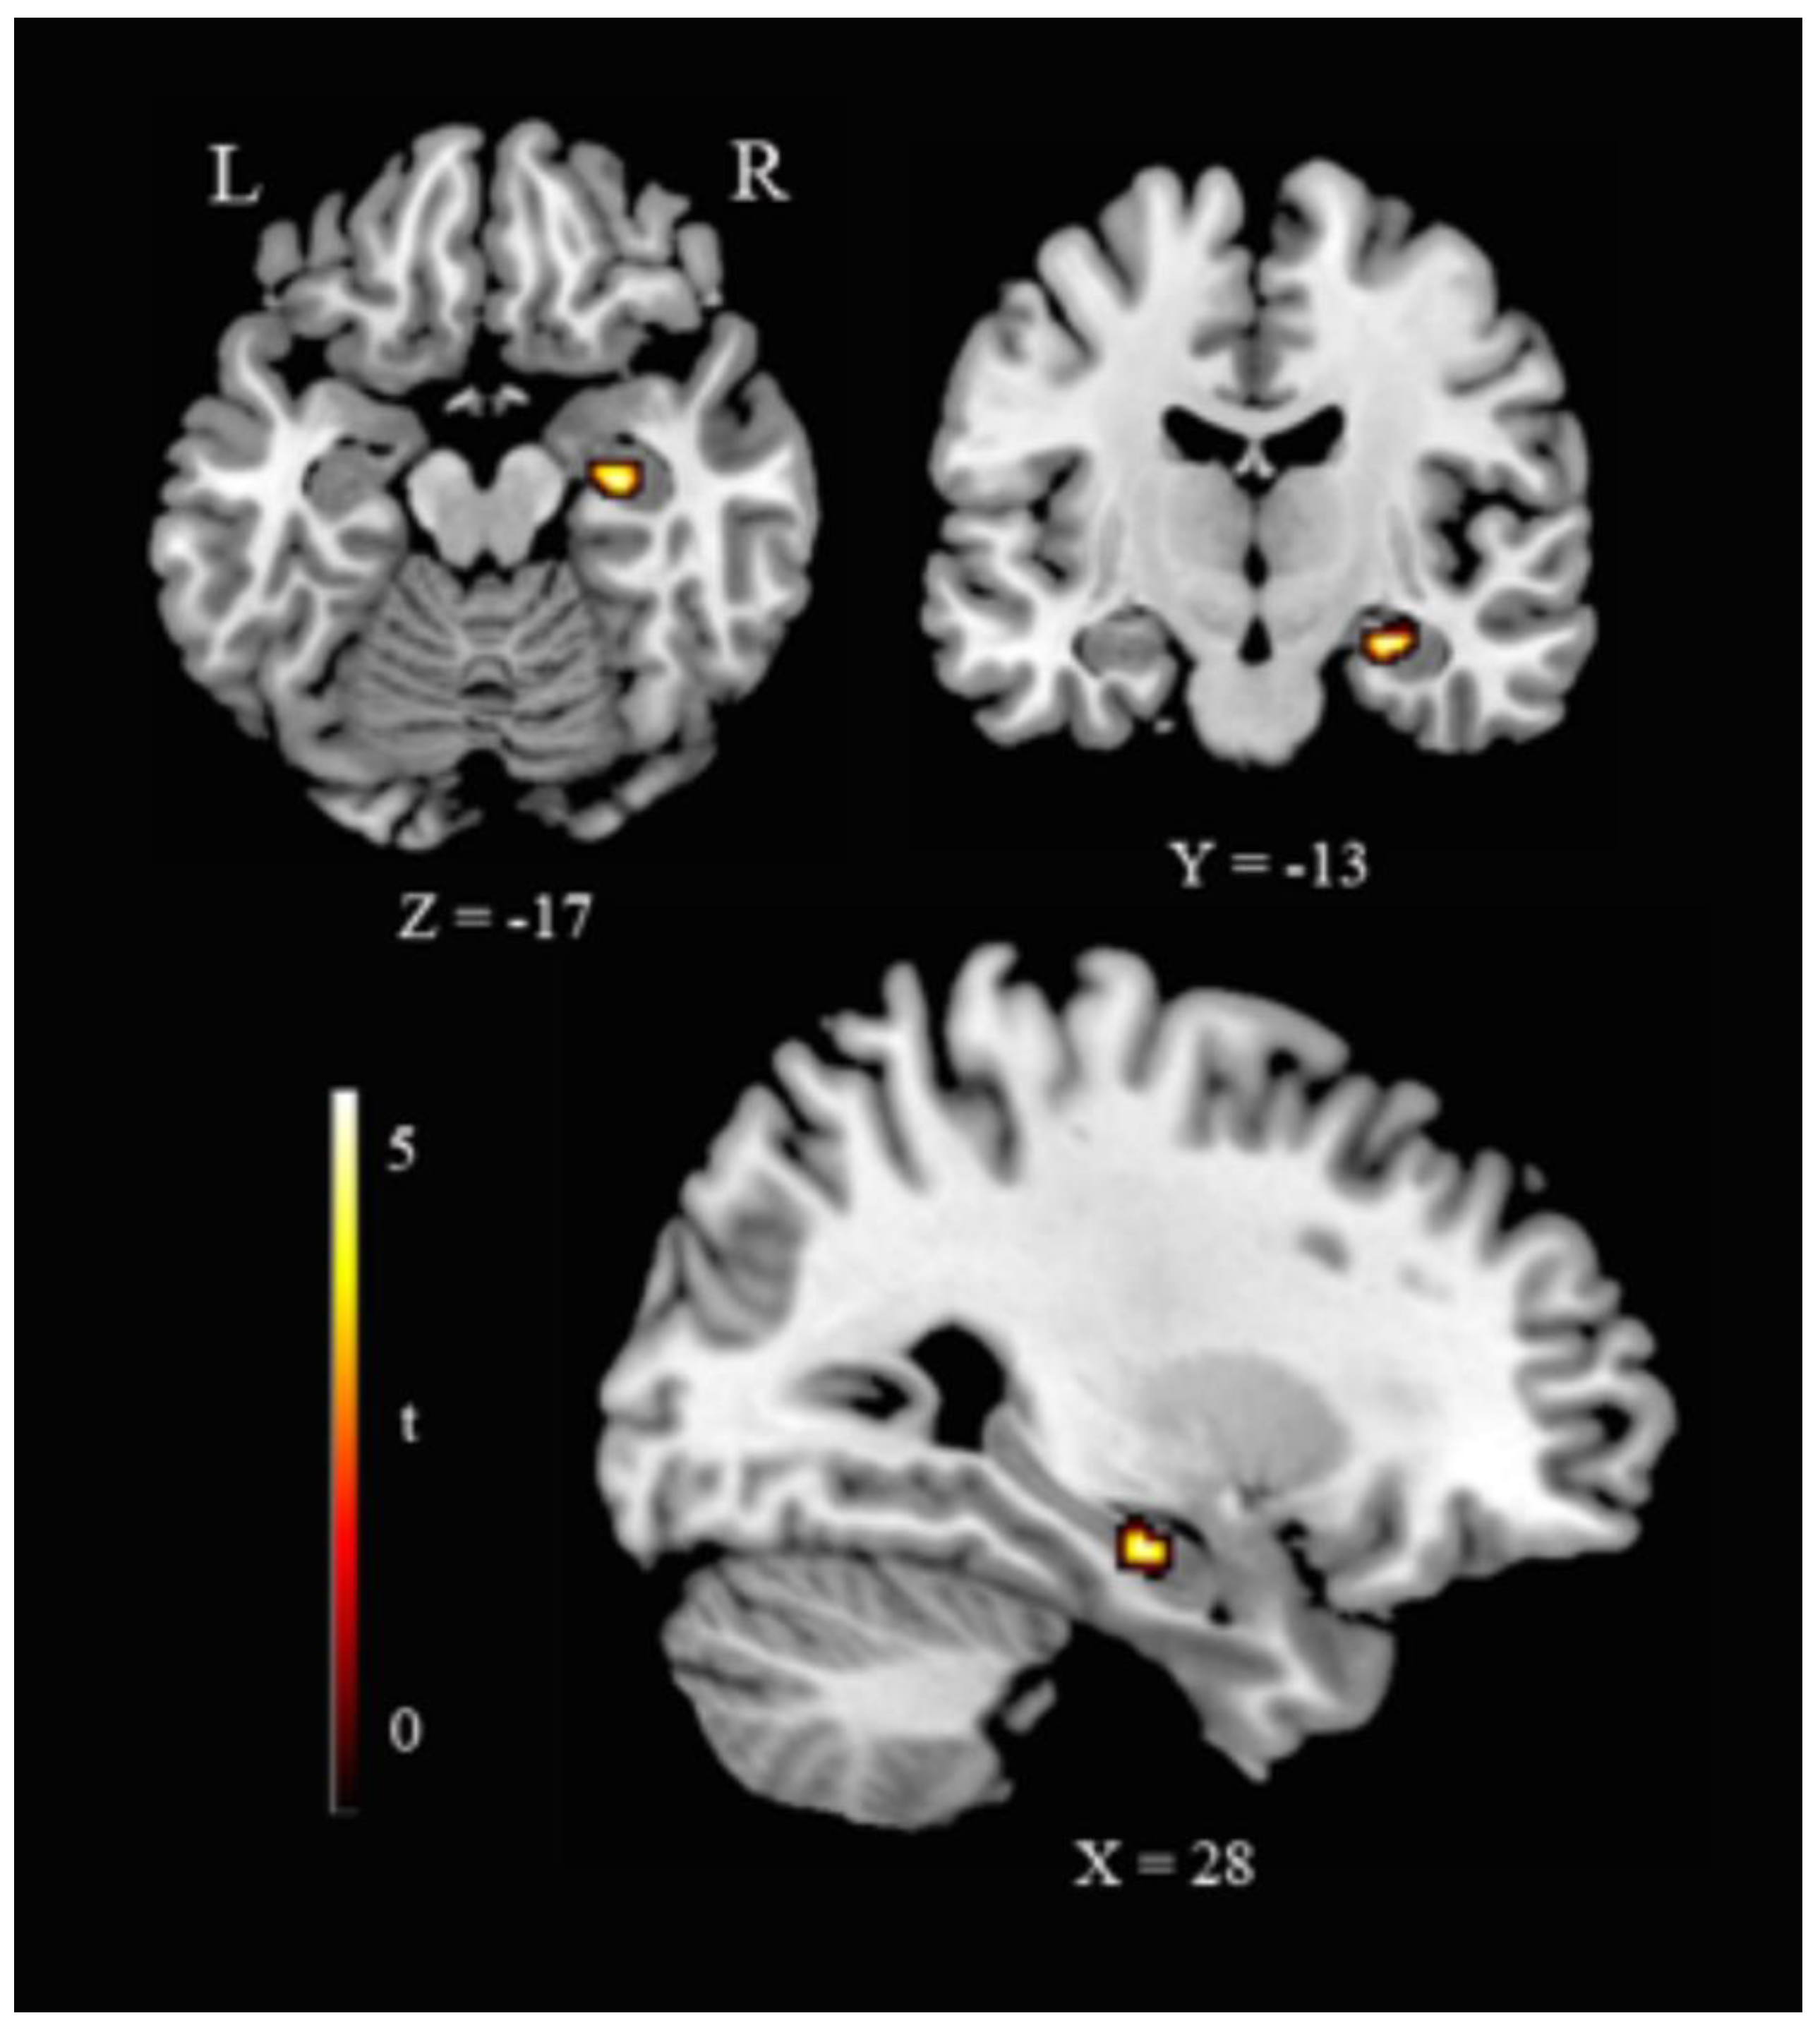

3.3. Hippocampus–ROI Analyses